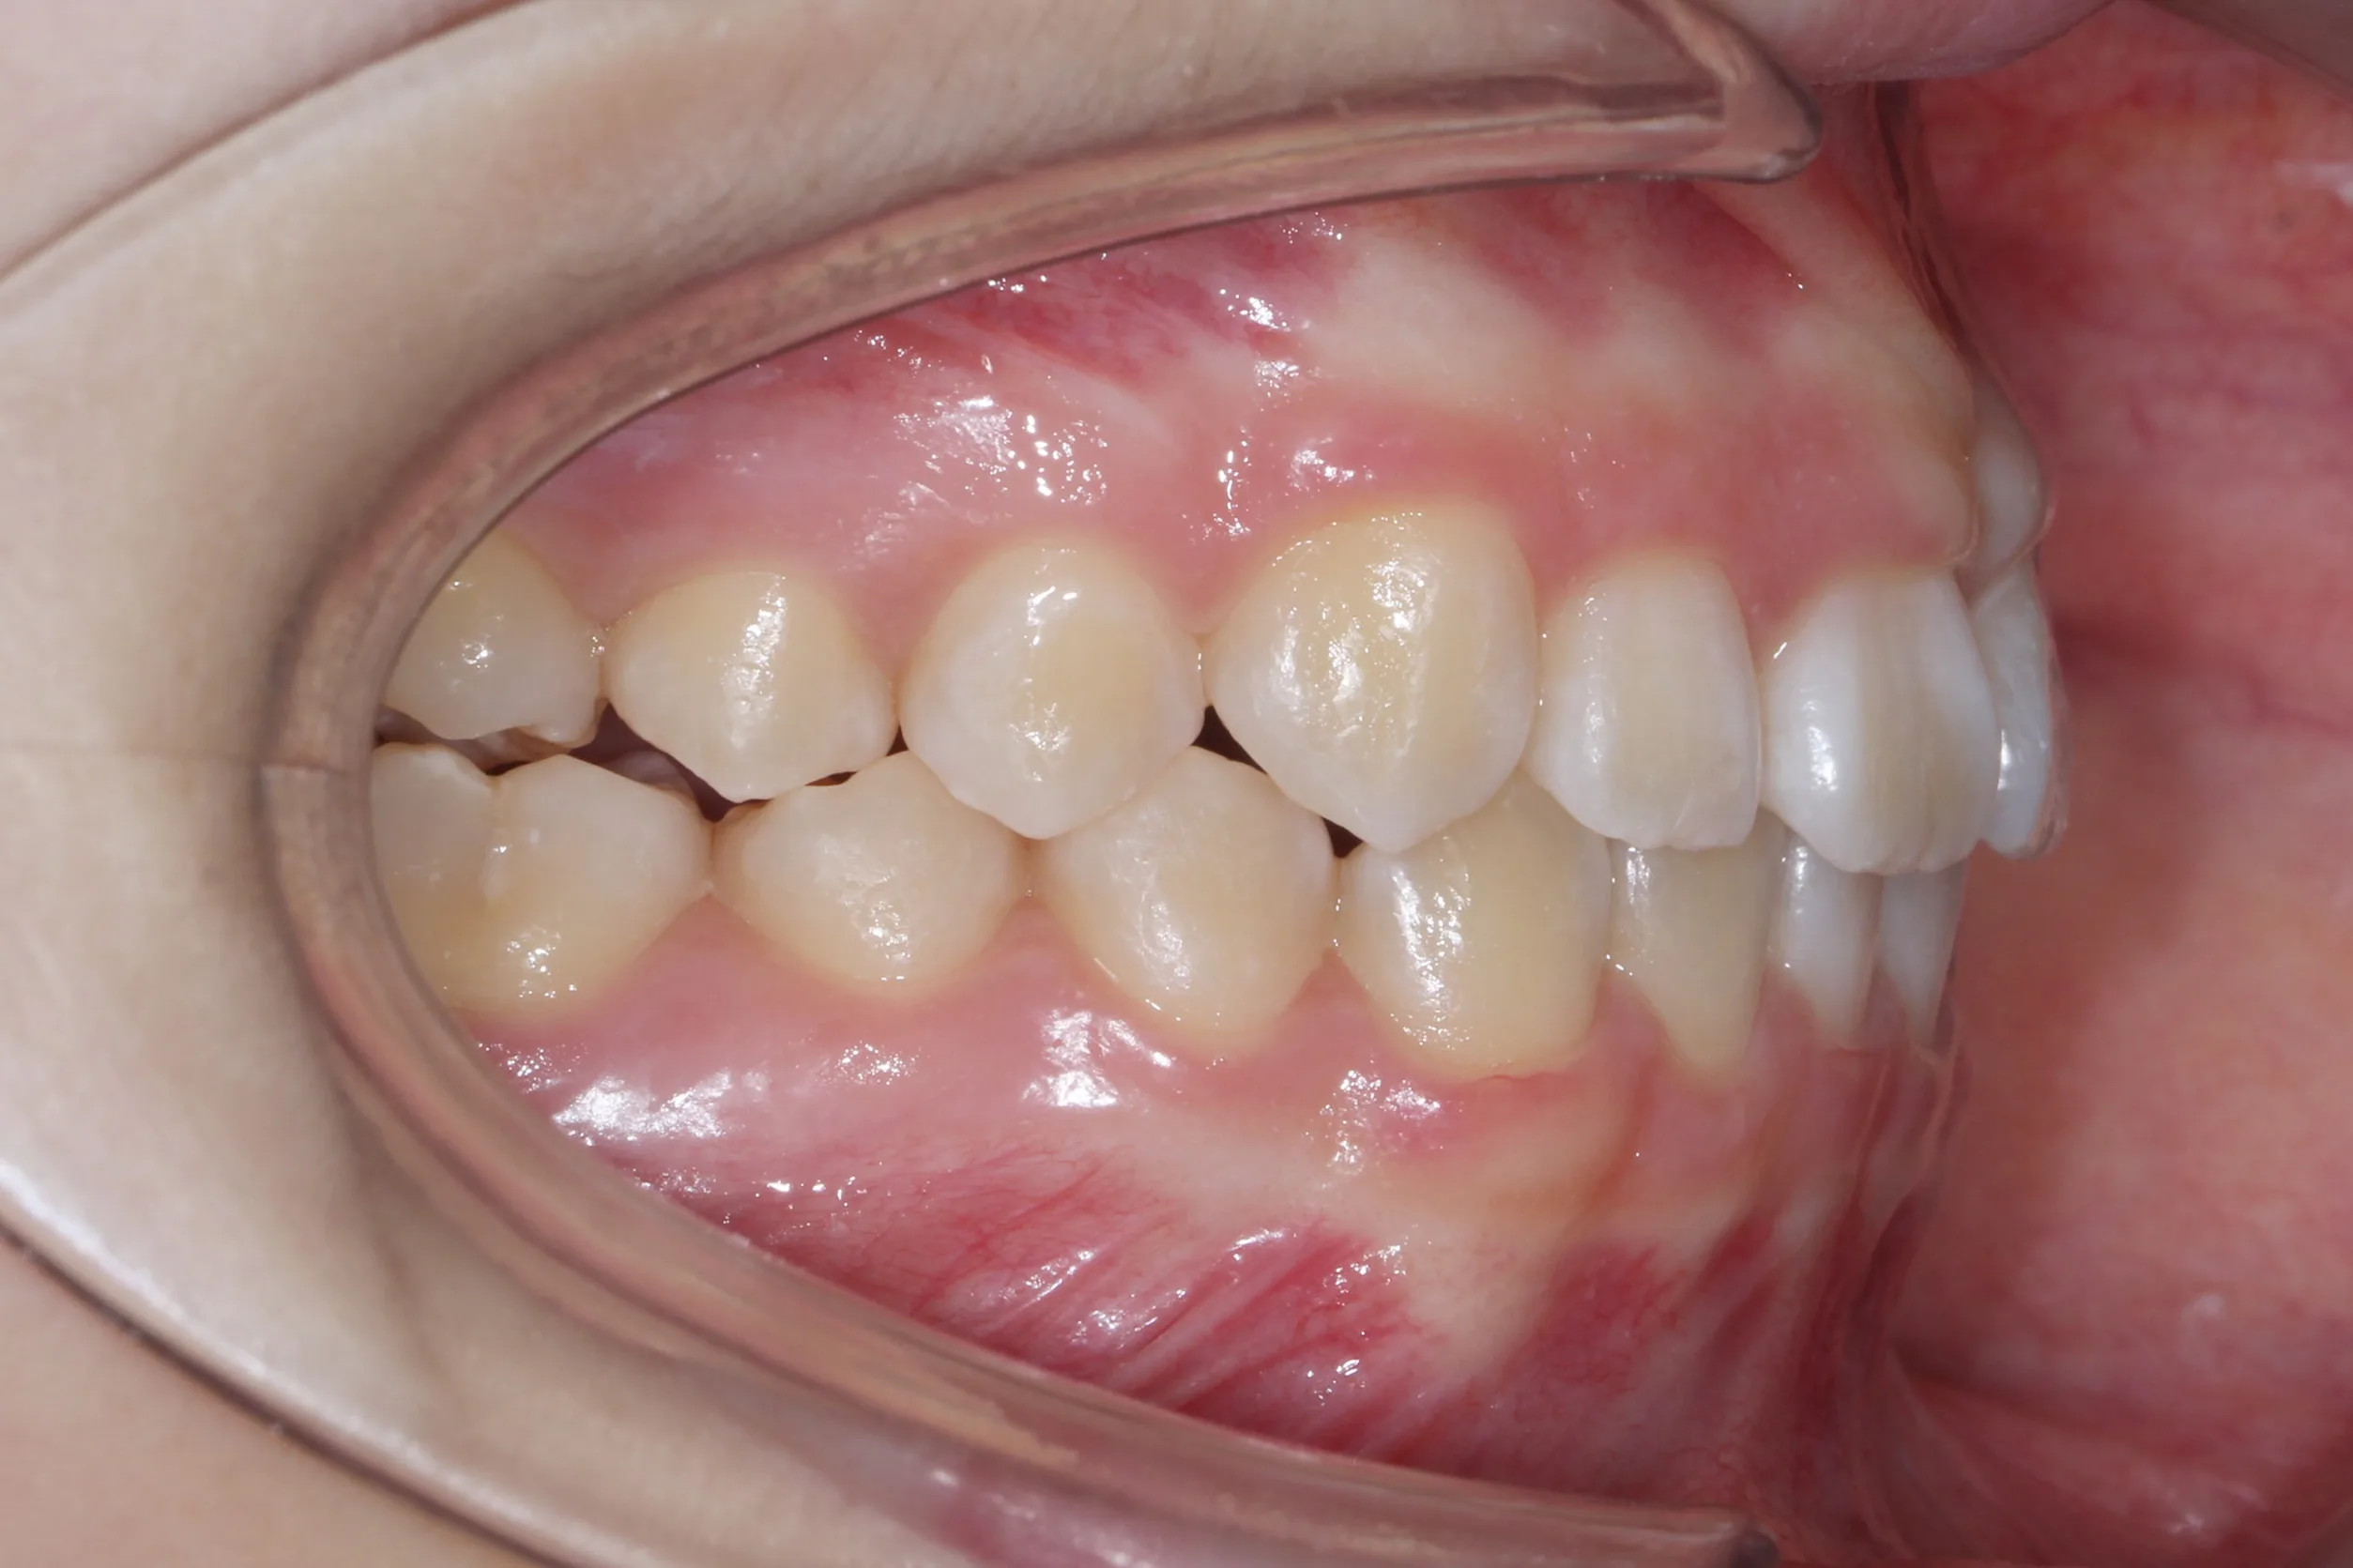

2년 7개월의 치료 과정을 거치며 환자분의 협조도 덕분에 안모 프로파일과 교합이 안정적으로 개선되었습니다. 성장기라고 해서 무조건 교정이 어려운 것은 아닙니다. 적절한 시기에 맞춤형 장치를 선택한다면 골격적 불균형을 효과적으로 바로잡을 수 있습니다.